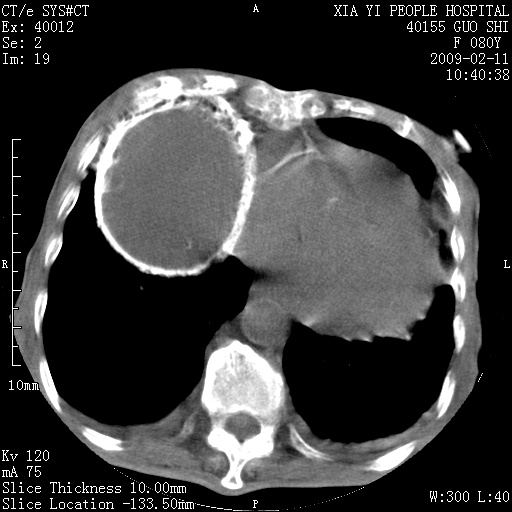

以下是引用随光逐影在2009-2-16 16:34:00的发言:[br]1)考虑右前纵隔皮样囊肿。2)双侧少量胸腔积液。

以下是引用zjzjr在2009-2-16 17:30:00的发言:[br]支持囊性畸胎瘤 双侧少量胸腔积液。